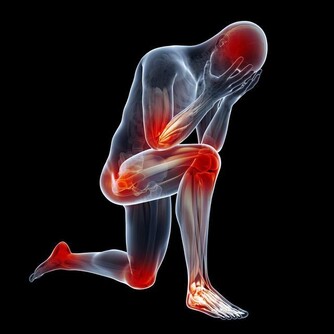

6. 前列腺癌:尿頻

前列腺癌是男性特別常見的癌症,早期往往沒有症狀,但一些前列腺癌會局部擴散,導致某些症狀出現,比如尿頻、尿急等尿路症狀。如果腫瘤更具侵襲性,或者前列腺癌已經轉移的男性,還會出現疲勞、疼痛、虛弱、麻木、摔倒、入睡困難、日常活動困難等症狀。